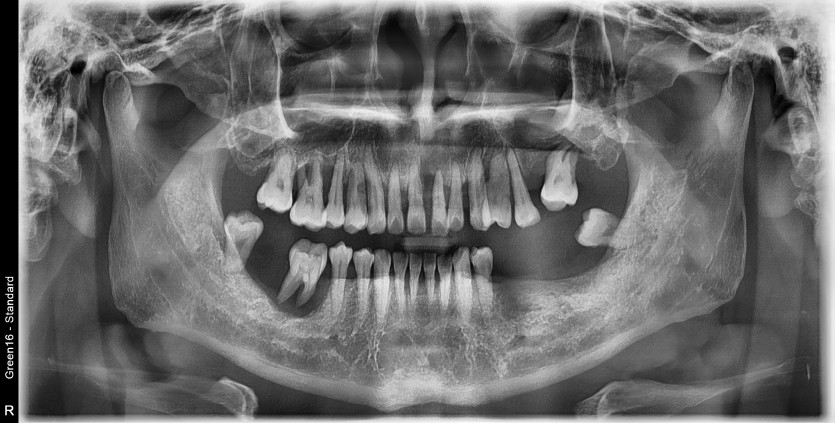

전체 임플란트 증례입니다.

17개의 임플란트로 완성하였습니다